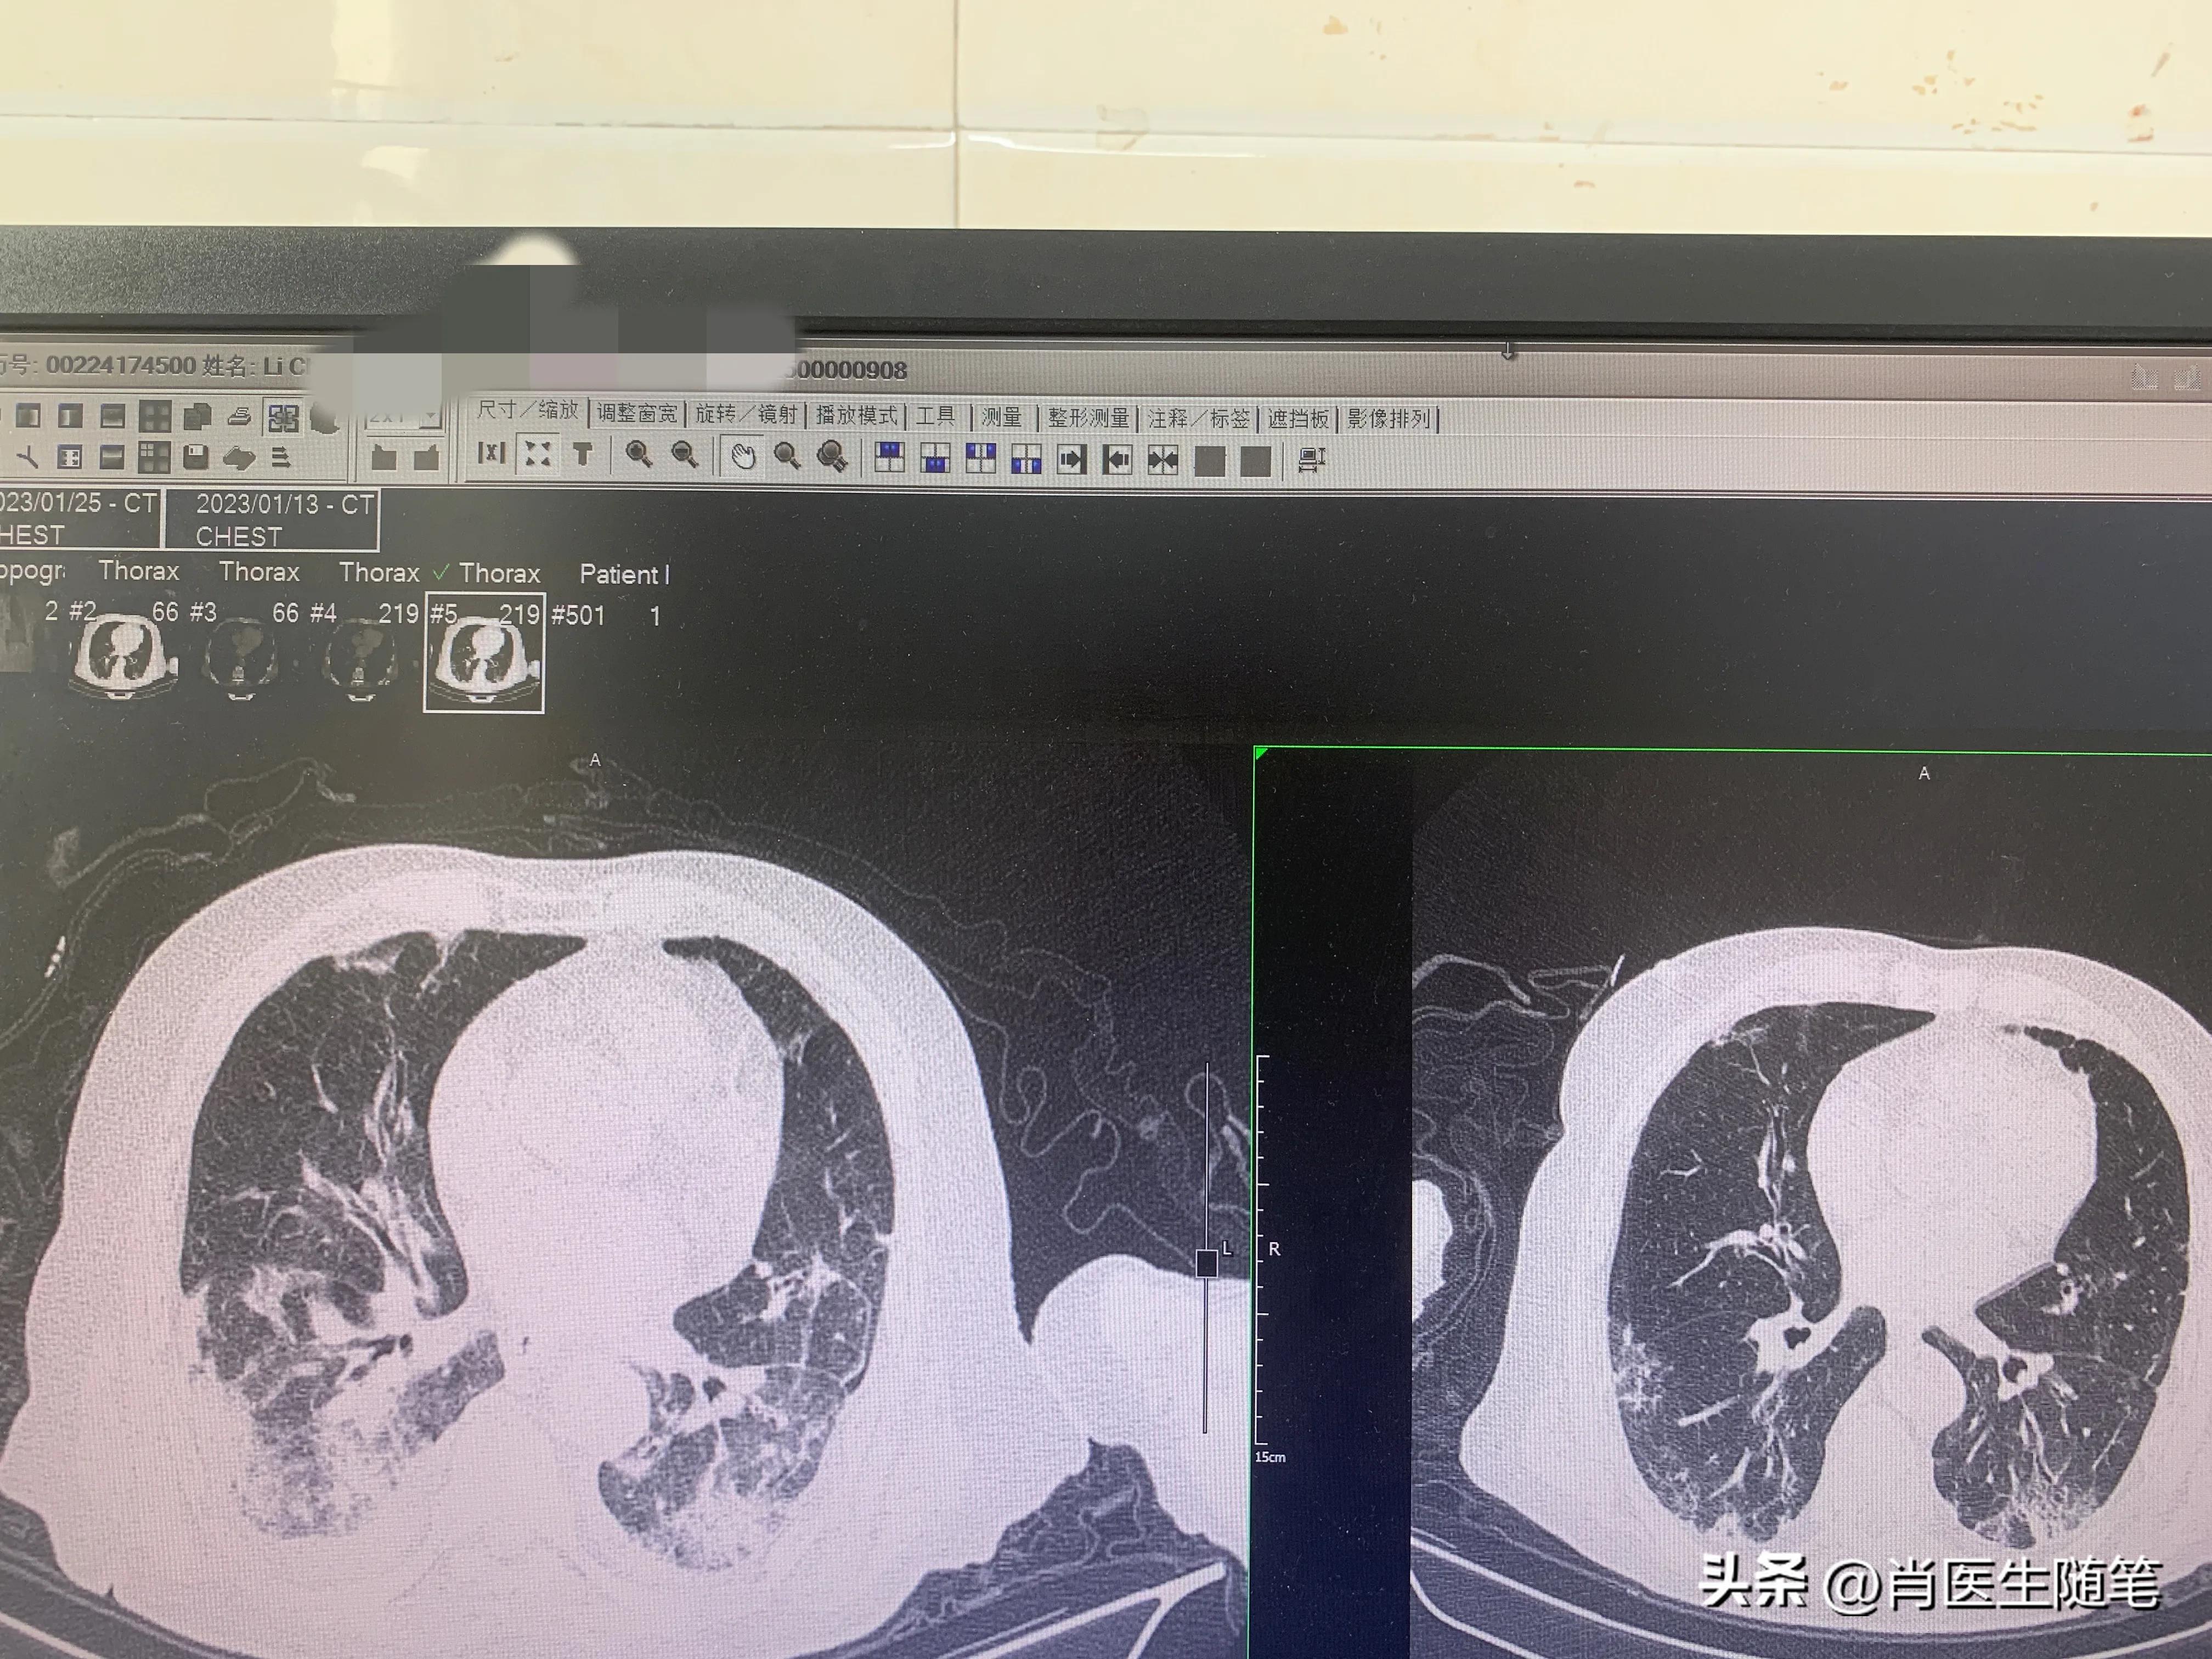

入院后2023-01-13胸部CT提示双肺炎症,纵膈多发淋巴结显示,部分钙化,双侧胸腔积液,心包积液。血提示炎症指标升高,白蛋白略低,33g/l。血氧饱和度吸氧下95%。

治疗后(2023-01-25)复查胸部CT,炎症较前吸收,下图是同样切面对比图。左边是13号的,右边是25号的。